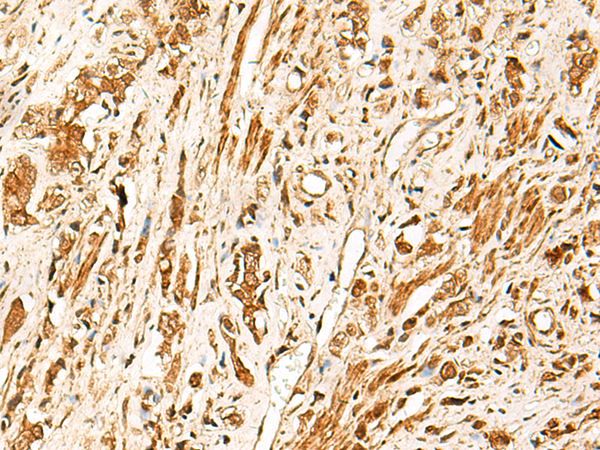

分类: 科研抗体货号: P04212别名: SREBP2; bHLHd2; SREBP-2应用: IHC反应种属: Human, Mouse, Rat